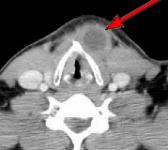

HELICAL CT FINDINGS: The CT scan was performed on AIC’s Multi-slice, Multi-detector Helical CT Scanner with 2.7 mm axial sections at 2.5 mm intervals before and during infusion of low-osmolar, non-ionic contrast using a power injector. It shows a lobulated cystic mass (arrows) in the neck at and below the hyoid bone in the midline and to the left of it, with portions of it behind the hyoid bone and portions embedded in the left strap muscle.